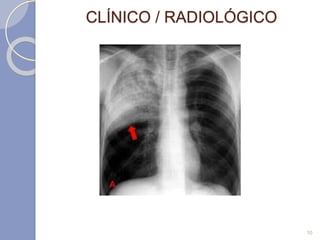

CLÍNICO / RADIOLÓGICO

10